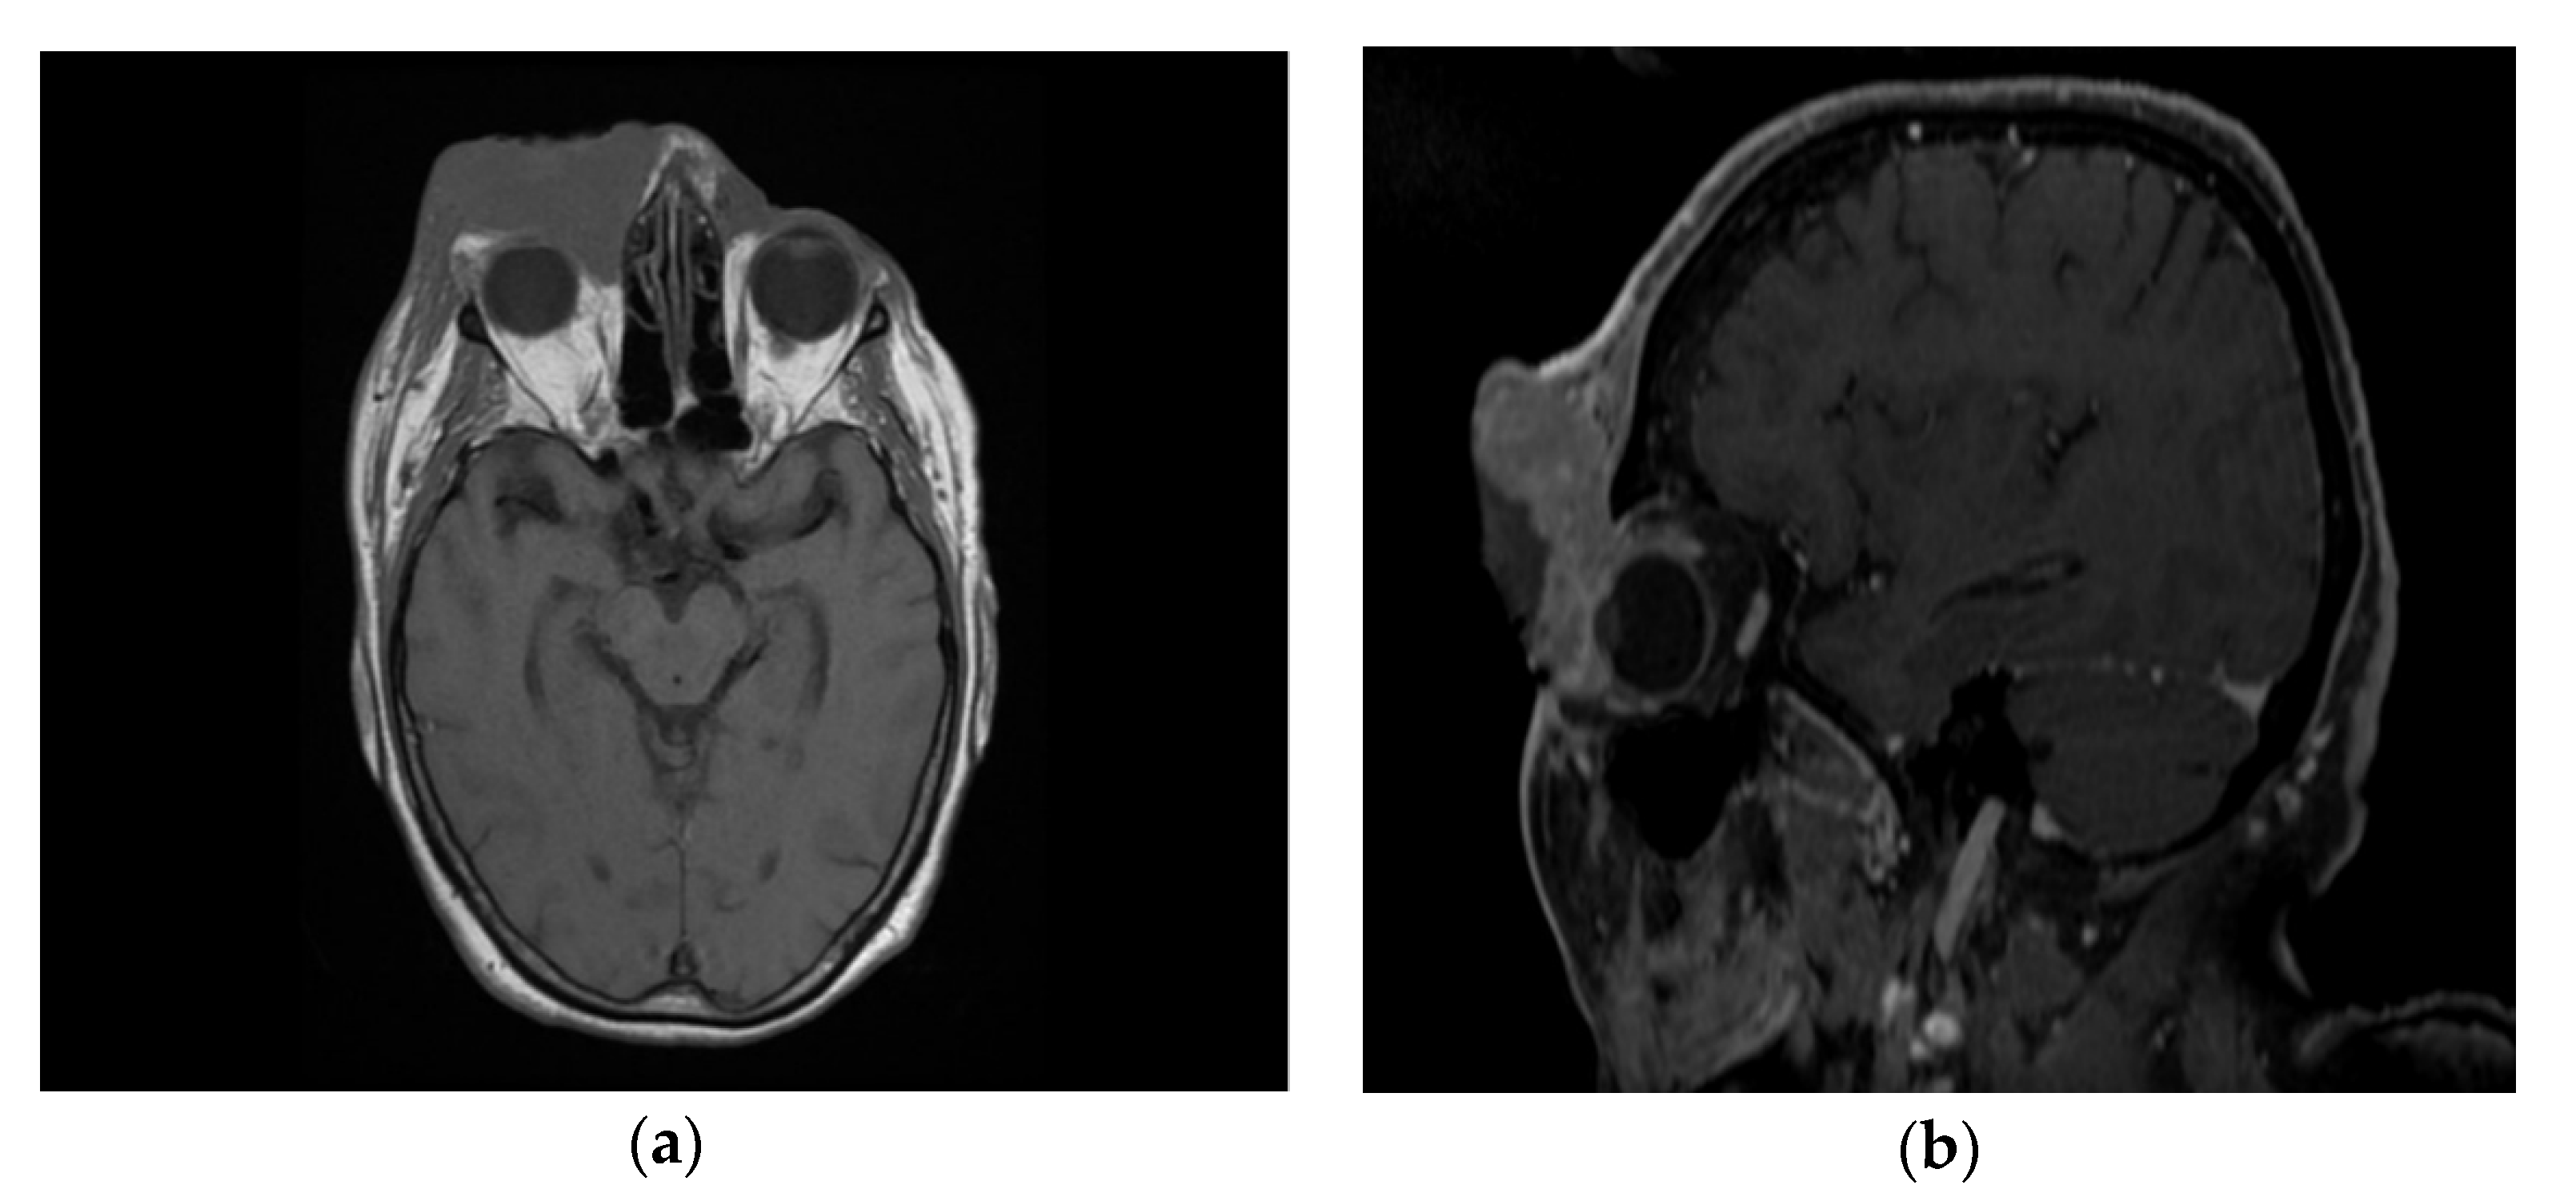

Following the immunohistochemical study, we obtained the following conclusive results. The tumor cells were intensely positive for CD3 (Figure 3b) and CD7 (Figure 3g), a relatively large number of tumor cells were positive for CD2 (Figure 3d) and CD4 (Figure 3e), and only a small population of T lymphocytes or some atypical larger cells were positive for CD8 (Figure 3f), with a CD4+/CD8+ ratio favoring CD4+ cells. Tumor cells were negative for CD30 (Figure 3i), CD5 (Figure 3c), and CD 56 (Figure 3h). A small population of atypical lymphocytes were positive in granzyme B after immunohistochemical staining. The cell proliferation index quantified by immunolabeling for Ki-67 was estimated and quantified at 80–85% (Figure 3j). Following the morphological examination correlated with special stains, the diagnosis of primary cutaneous T-cell lymphoma NOS was established. Whole-body CT was performed and revealed tumor formation in the soft epicranial parts, right frontal area, and supraorbital area, with dimensions of 22/50/45 mm. The lesion affected the upper eyelid and the paranasal region, with no signs of ocular or intracranial invasion. In the frontal on the median and parasagital line on the left, epicranial area, adjacent to the described lesion, another structure with 35/15 mm contrast socket was highlighted. The dynamic contrast-enhanced magnetic resonance imaging (MRI) revealed a large, inhomogeneous lesion, with infiltrative, invasive contour. The origin of the tumor was most probably from the periorbital superficial tissues, with invasion in the orbit and direct contact to the anteromedial aspect of the ocular globe without the presence of a cleavage plane between the two structures (Figure 4a,b and Figure 5a,b). Figure 4a shows that the T1 FSE (fast spin echo) axis and sagittal T1 FSE contrast-enhanced with fat-saturation sequence was not enhanced (a), whereas Figure 4b shows inhomogeneous enhancement of the lesion, with superficial tissue origin and invasion in the right orbit. Figure 5a,b depict the axis T2 PROPELLER sequence showing the necrotic areas in the primary and secondary lesion, satellite lesion in the superficial tissues of the frontal region (marked by arrows in the picture). A restricted diffusion on diffusion weighted imaging (DWI) sequences was observed, with an apparent diffusion coefficient (ADC) value of 0.873 × 10−3 mm2/s on the ADC map (Figure 6a). Dynamic contrast-enhanced MRI (DCE-MRI) imaging showed a type III (C) curve highly suggestive for malignancy (Figure 6b), and a high constant transfer (ktrans) value was observed, pointing to a possible good response to radiochemotherapy (Figure 7). In the proximity of the left frontal area, two nodular superficial lesions were identified, suspected of secondary nodules.

Figure 4. Ax T1 FSE non-enhanced (a) and sagittal T1 FSE contrast-enhanced with fat-saturation sequence (b). Inhomogeneous enhancement of the lesion, with superficial tissue origin and invasion in the right orbit.